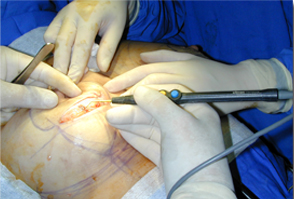

適用于細(xì)微、精細(xì)的切割如頭頸部,敏感部位皮膚的切割。

適合于皮下組織的切割和剝離。

特別是在運(yùn)血較為豐富的部位。